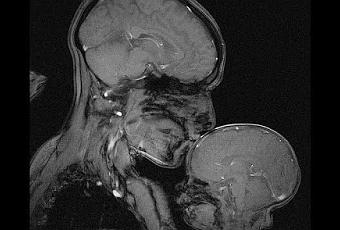

Nota: La foto es una imagen de resonancia magnética, un solo corte. Muestra a una madre con su hijo dormido, fue necesaria mucha quietud para obtenerla. Es algo que no se ve todos los días pero que ilustra perfectamente que lo que pensamos que es un límite es algo puramente figurado.